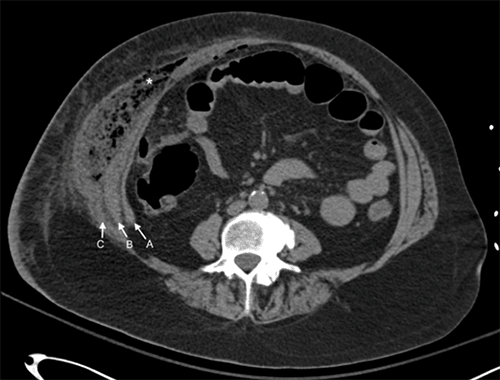

Initial computed tomography (CT) study of the abdomen revealed several large gas and fluid collections in the pelvis, intraperitoneal inflammatory changes in the right lower quadrant, and wall thickening throughout the sigmoid colon with adjacent fluid collections. There was a large 4 × 8 × 14 cm gas and fluid collection in the abdominal wall musculature interposed between the internal and external oblique muscles (Figure 1 and Figure 2). A CT of the thorax revealed extensive gas in the right chest wall with pectoralis, serratus anterior muscle, and subcutaneous tissue involvement, suggesting necrotizing soft tissue infection (Figure 3). Physical exam revealed induration and erythema extending from the right flank to the epigastrium and down to the right lower quadrant without obvious necrotic skin or soft tissue.

Figure 2. Axial CT Imaging of Abdomen. Published With Permission

Gas and fluid collection seen between internal and external oblique muscles. Abscess cavity marked by asterisk (*) (A: transversus abdominus; B: internal oblique muscle; C: external oblique muscle)